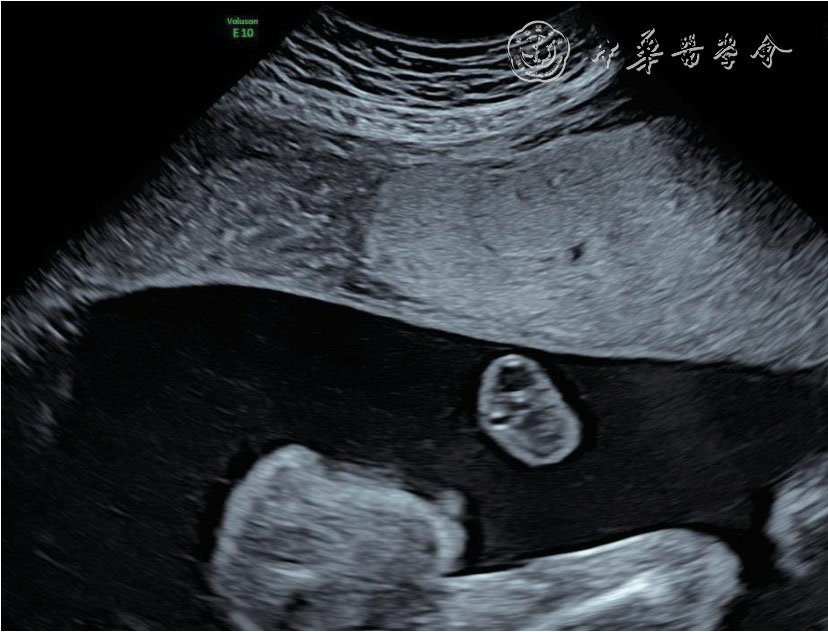

26 例TAPS 均在中晚孕期(孕17+1~34+6 周)超声检查中发现,其中Ⅰ期11 例,Ⅱ期3 例,Ⅲ期3 例,Ⅳ期9 例,Ⅴ期0 例。共有的超声特征为:(1)供血儿MCA-PSV 增高(>1.5 MoM),受血儿MCA-PSV 降低(<1.0 MoM)( 图1);(2)“黑白”胎盘:供血儿脐带入口附近胎盘回声增强、增厚,受血儿脐带入口附近胎盘回声减低、较供血儿侧薄(图2)。其他超声特征包括:(1)24例(92%)受血儿肝呈“星空征”(图3);(2)4例(15%)供血儿肠管回声增强(图4);(3)22例(85%)心脏异常,包括心胸比增大、房室瓣反流、房室瓣频谱呈单峰、心肌增厚等征象(图5a、5b);(4)18 例(69%)多普勒血流异常,包括脐动脉、脐静脉、静脉导管A 波异常等;(5)9 例(34%)胎儿水肿,包括皮肤水肿、胸腹腔积液、心包积液;(6)15 例(57%)羊水量不均衡;(7)19 例(73%)脐带异常,包括脐带水肿、脐带插入点异常(图6);(8)15 例(57%)合并双胎选择性宫内生长受限(selective intrauterine growth restriction,sIUGR)、TTTS(表1)。对供血儿及受血儿其他超声特征进行统计分析发现,受血儿肝“星空征”、脐带水肿,供血儿肠道回声增强、胎儿水肿、心胸比增大特征比较,差异有统计学意义(P<0.05,表2)。

图2 双胎贫血-红细胞增多序列征胎儿孕22+5 周产前超声图像可见供血儿脐带入口附近胎盘回声增强、增厚,受血儿脐带入口附近胎盘回声减低、较供血儿侧薄